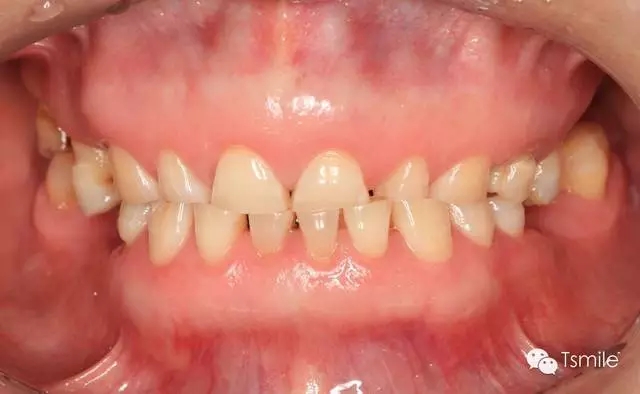

圖1: 夜磨牙導(dǎo)致的牙列重度磨耗

磨耗是指在下頜的功能運(yùn)動(dòng)(咀嚼食物等)或副功能運(yùn)動(dòng)(夜磨牙、緊咬牙等)過(guò)程中上下頜牙齒和牙齒之間的機(jī)械摩擦而導(dǎo)致的牙齒表面硬組織的缺損。

磨耗患者一般有特定的飲食習(xí)慣,如喜吃硬食、嚼檳郎等,這些飲食習(xí)慣導(dǎo)致咀嚼時(shí)咬合力過(guò)大,或者牙齒咬合面之間粗燥的事物導(dǎo)致牙面承受過(guò)度的機(jī)械摩擦;磨耗患者一般還有夜磨牙、緊咬牙等副功能運(yùn)動(dòng)病史。